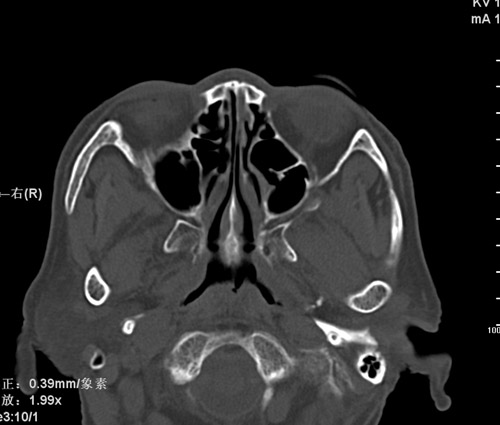

标题: CT17755:女,74 左鼻旁肿胀半年,临床以左上颌窦旁占位行CT [打印本页]

标题: CT17755:女,74 左鼻旁肿胀半年,临床以左上颌窦旁占位行CT

ct考虑鼻前庭囊肿 或鼻翼基底部慢性炎症,左上颌窦少许炎症 请指教

1)考虑左侧鼻前庭囊肿并感染。2)双侧上颌窦炎。

左侧鼻前庭囊肿并感染。双侧上颌窦炎。支持